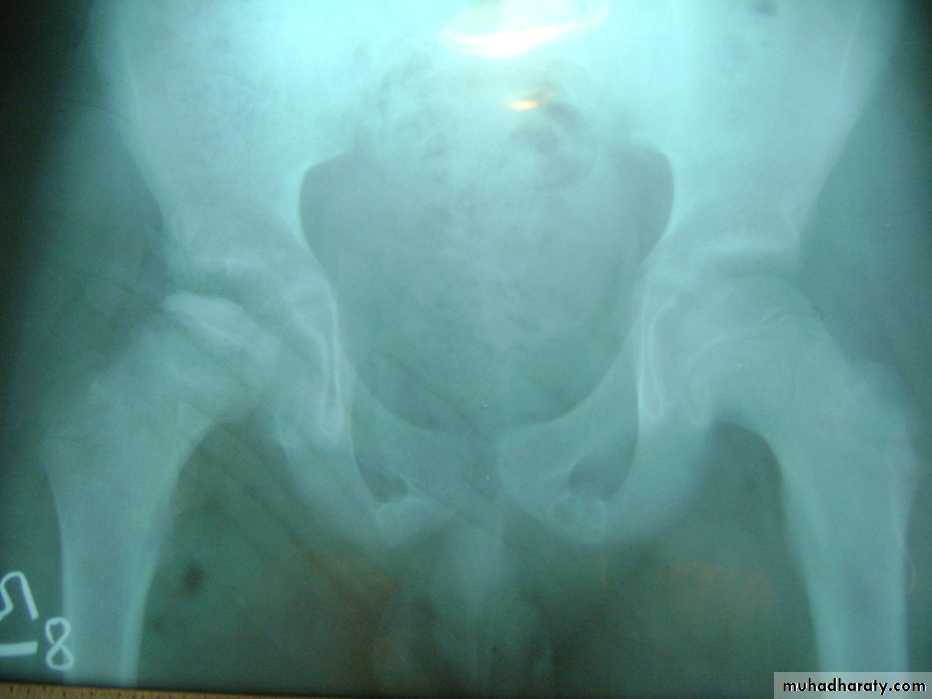

Slide 21- Give two differential diagnosis?2- Mention two physical examination you can use it in such condition.